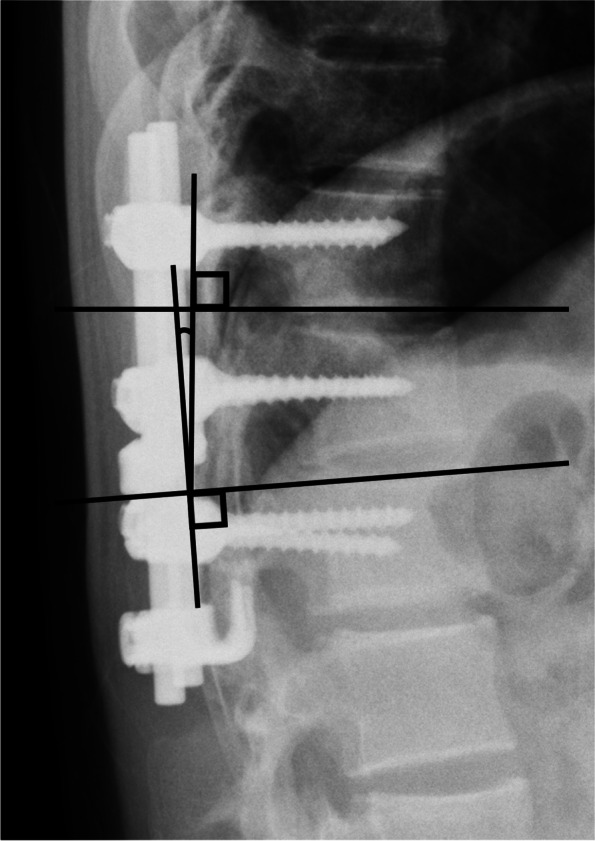

Radiographic assessment was performed using lateral thoracolumbar spine radiographs taken at four timepoints: at the time of injury, after posterior pedicle screw fixation, before implant removal, and at final observation (Fig. 1). Kyphotic angle was defined as the Cobb angle of the lower endplate line of the cranial vertebral body and the upper endplate line of the caudal vertebral body based on the fractured vertebral body (Fig. 2). The vacuum phenomenon was evaluated on sagittal CT images before implant removal (Fig. 3). All measurements were made by a board-certified orthopedic surgeon who was not involved in the patients’ care.

Fig. 2.

Kyphotic angle